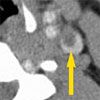

Suppurative jugular venous thrombosis with emboli to the lungs, or Lemierre syndrome, was suspected based on the lung abscess, anaerobic septicemia, and sore throat prodrome. A CT scan of the neck demonstrated a filling defect of the jugular vein, which confirmed the diagnosis (Figure 2).